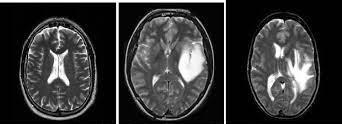

(a)Glioma(b)Pituitary(c)Meningioma(d)Normal

Fig.4. Sampleofimagesfromeachclassofbraintumours generatedfromtheMRI.